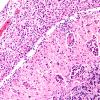

NEOPLASMS (HEMATOLYMPHOID)

Lymphoma, secondary (6)